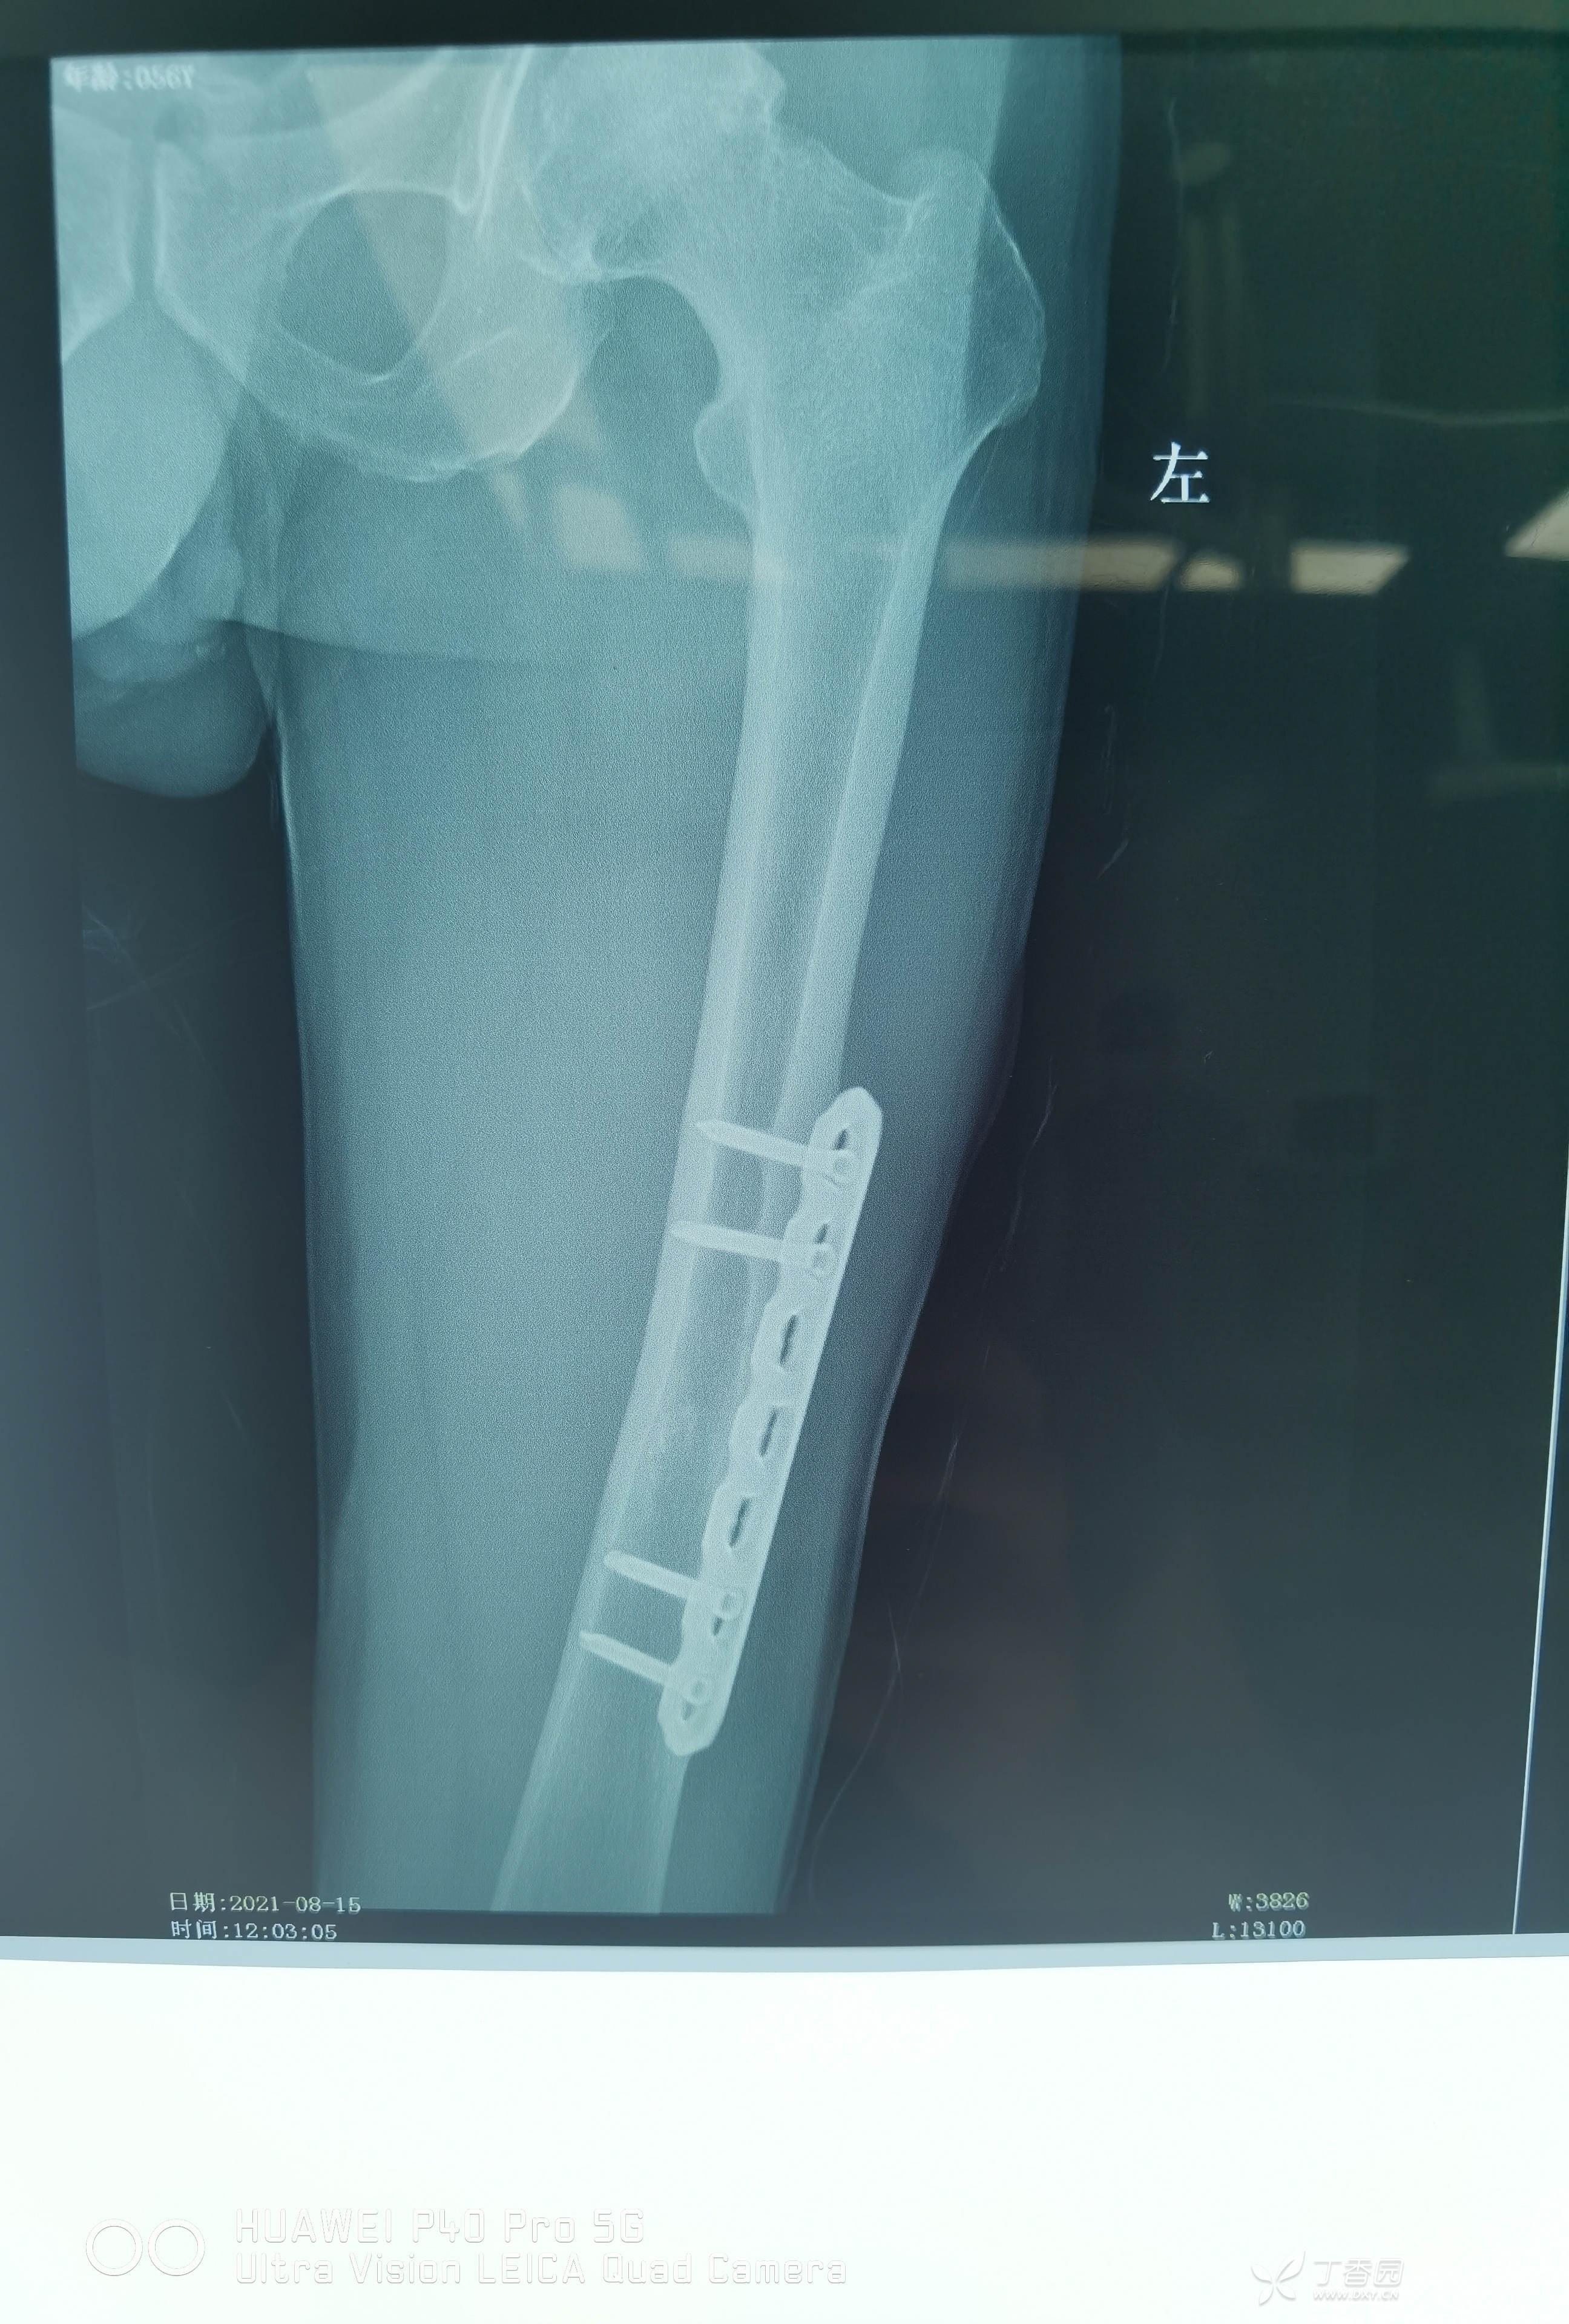

2021.08.15门诊来院,如下图:骨折愈合良好。查体未发现明显异常,各关节活动良好。

看当时术后片子,为患者捏了一把汗。

患者也是真幸运,因为股骨颈骨折,卧床了四个月,最后一直双拐保护辅助行走,最终股骨干顺利愈合。